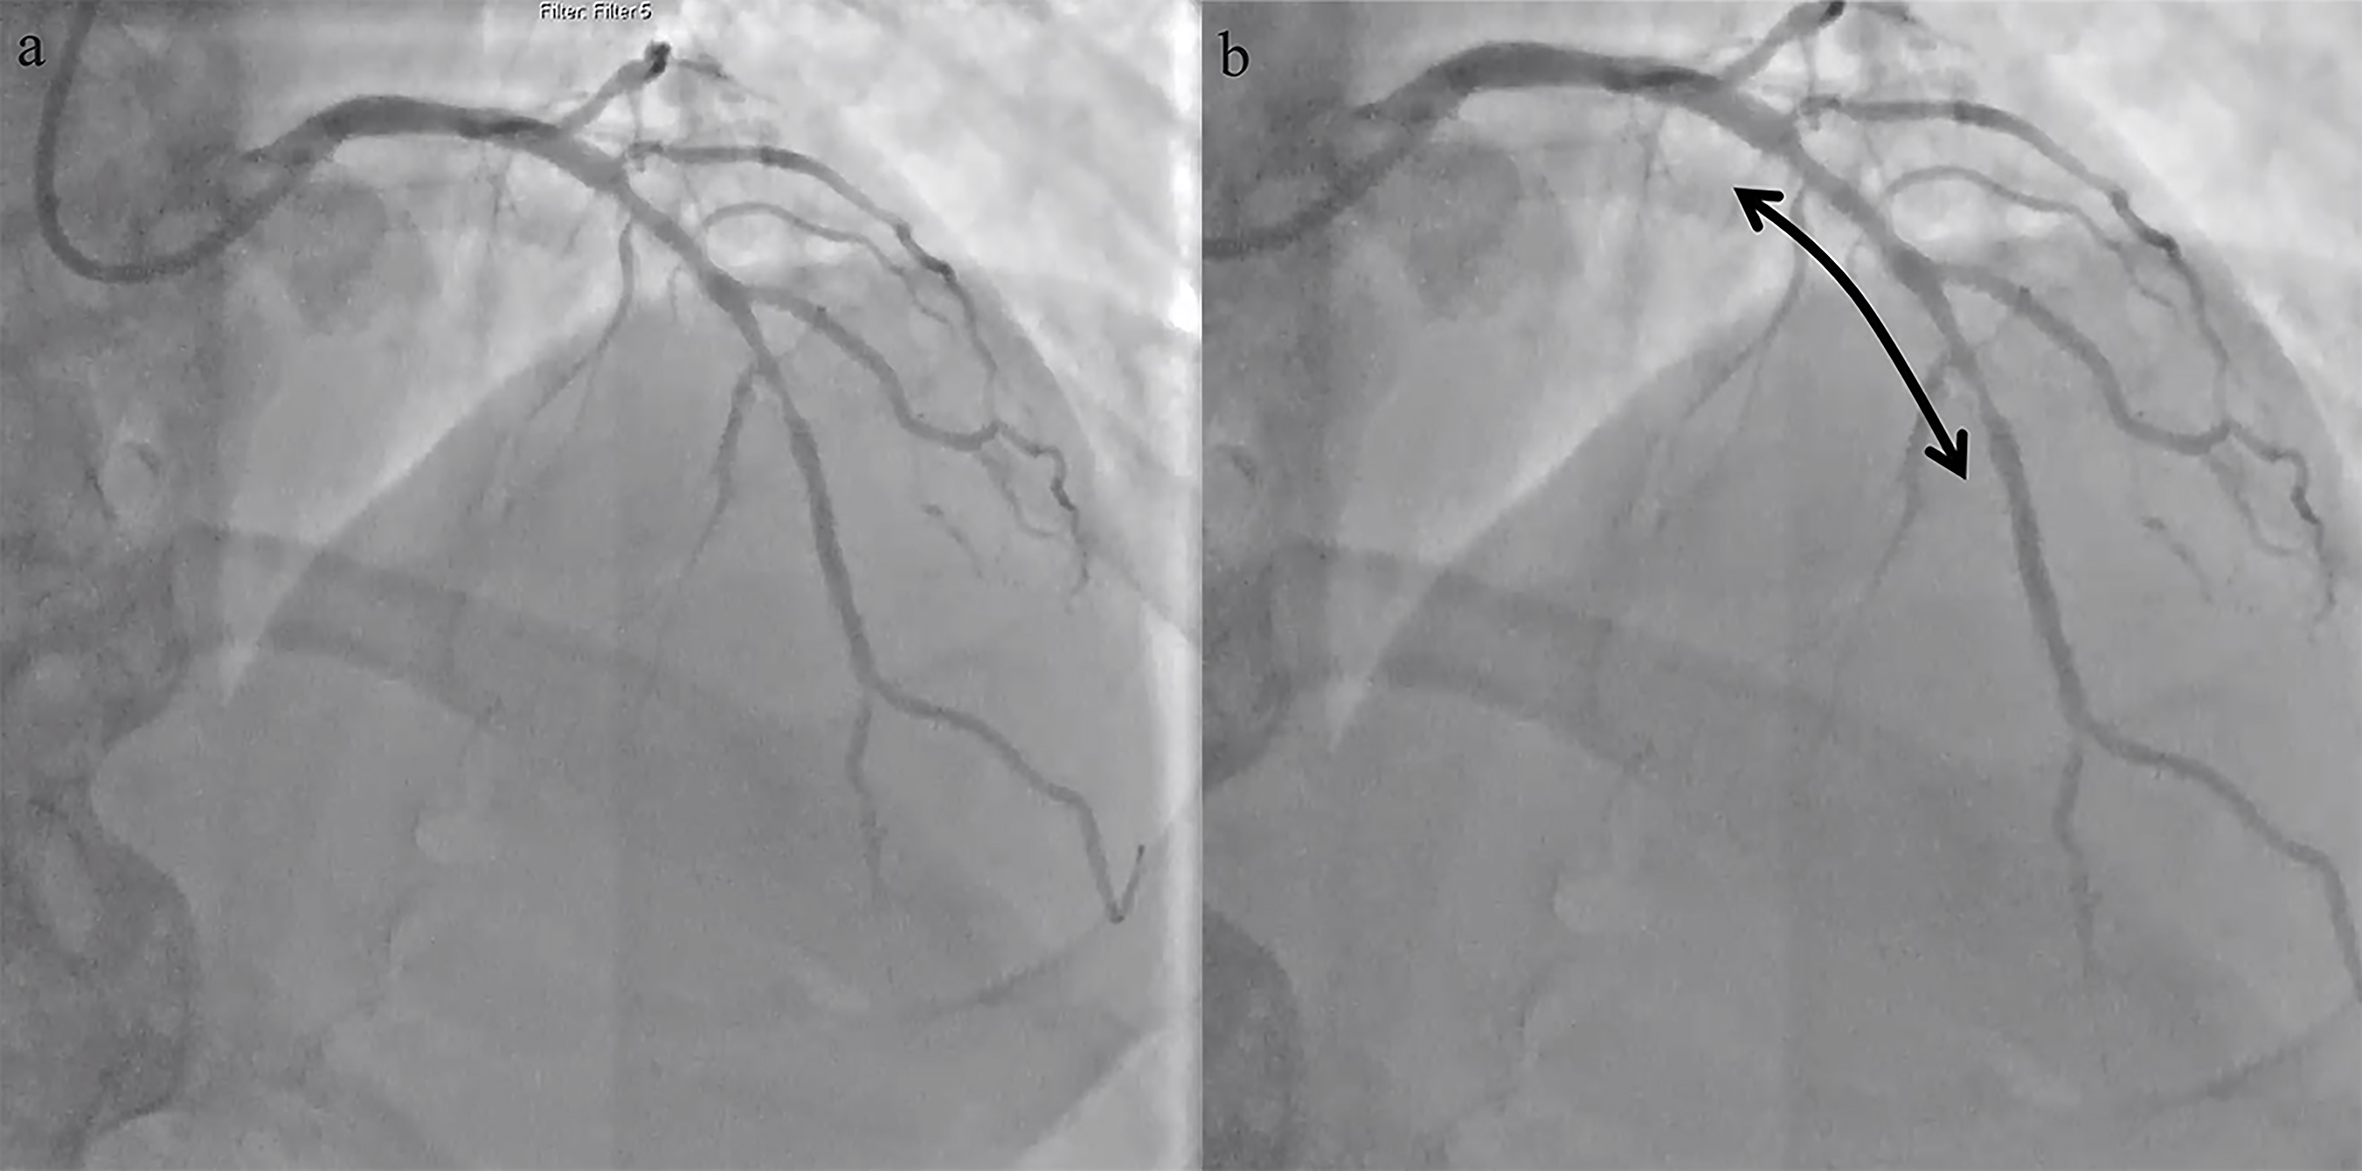

A 62-year old man awaiting cancer surgery and angina (CCS class III) was found

to have a significant ischaemia in the anterior wall of the left ventricle on the

stress echocardiogram. His background included; hypertension, hyperlipidaemia and

previous smoking. At the time of presentation, he was on aspirin (primary

prevention), atorvastatin and amlodipine. The coronary angiogram demonstrated a

significant calcified disease in the mid-segment of left anterior descending

artery (Fig. 1). His haemoglobin was 90 gm/dL, but was stable. Trial of medical

Fig. 1.Coronary angiogram showing a significant calcified disease in the mid-segment of left anterior descending artery. (a) Coronary angiogram showing a significant calcified disease in the mid-segment of left anterior descending artery. (b) Arrow highlighting the lesion.